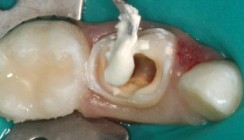

Bezug auf die Endodontie. Viele Kolleginnen und Kollegen in Deutschland

haben dazu nie eine Vorlesung gehabt und sind folgerichtig mit dem

Versuch, die Konzepte der Endodontie des bleibenden Gebisses auf die

Milchzähne zu übertragen, gescheitert. Das kann und muss im Interesse der

betroffenen Kinder besser werden.